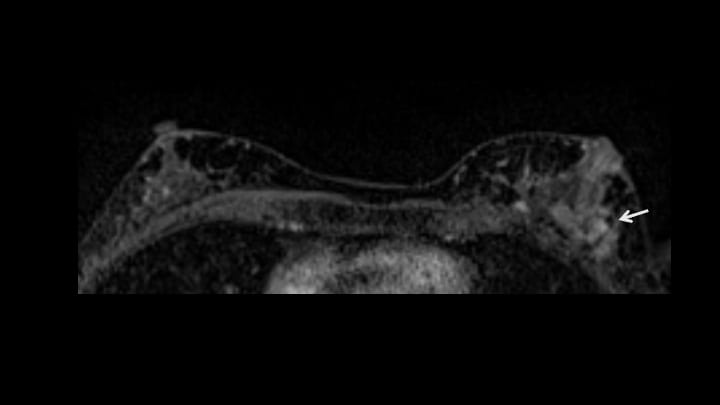

8. ダイナミックMRI 後期相

早期相と同様に左乳頭外側にnon-mass enhancement。